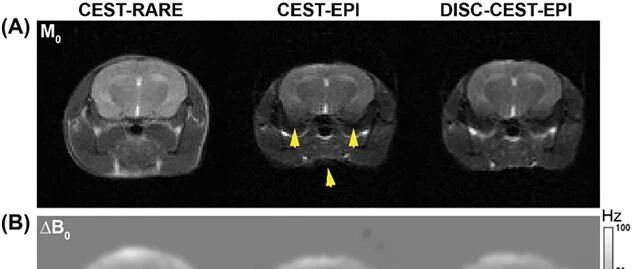

【推荐阅读】评估CEST-EPI中畸变自校正的有效性 布鲁克公司 · 公众号 · · 1 月前 · |